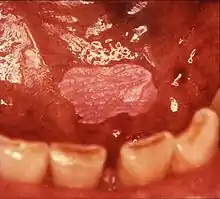

![]() | |

| Leukoplakia on the inside of the cheek. | |